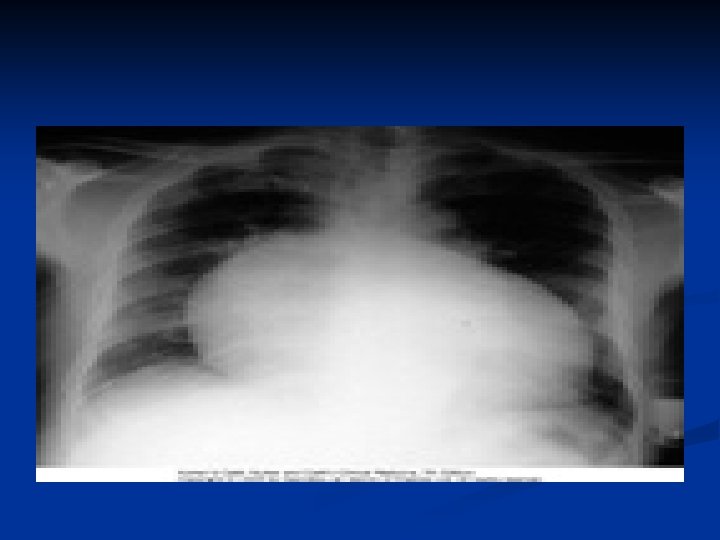

n n n CHEST RADIOGRAPHY The cardiac silhouette is normal until effusions are at least moderate in size. With moderate and larger effusions, the anteroposterior cardiac silhouette assumes a rounded, flasklike appearance. Lateral views may reveal the pericardial fat pad sign, a linear lucency between the chest wall and the anterior surface of the heart representing separation of parietal pericardial fat from epicardium. The lungs appear oligemic.